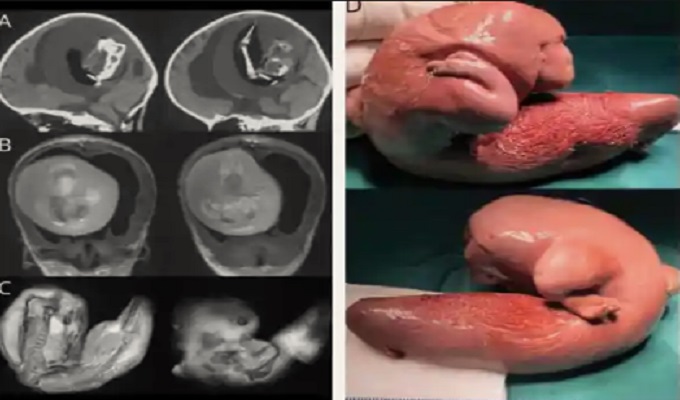

Los médicos de la Universidad de Fudan en Shanghái descubrieron a su "hermano" mientras atendían a la pequeña por dificultades en sus habilidades motoras y una cabeza anormalmente agrandada. A través de imágenes por tomografía computarizada (TC), se reveló que el cerebro de la niña estaba comprimido por el feto malformado de su gemelo.

A través de imágenes por tomografía computarizada (TC), se reveló que el cerebro de la niña estaba comprimido por el feto malformado de su gemelo.

Los casos de Fetus in fetu son extremadamente raros, con una incidencia de uno por cada 500 mil nacimientos, y aún más excepcionales cuando el feto se desarrolla en el cerebro de su gemelo. Aunque la evolución de la niña no fue detallada, los especialistas informaron que le extrajeron el feto de su gemelo de la cabeza y que su recuperación fue total, aunque no se especifica si sufrió daños a largo plazo.